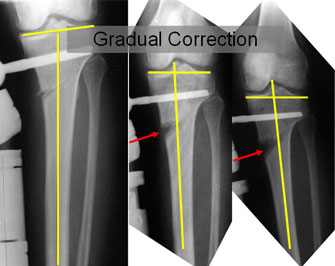

| The xray pictures during the gradual distraction process of high tibial osteotomy. |

| The picture on the left is taken after surgery, before the distraction is begun. The distraction is started 5-7 days after surgery. This helps in initiation of the healing process and better formation of regenerate. The lines drawn show the angle between the joint line of tibia and the anatomic axis of tibia. The inner angle is reduced in this case. |

| The picture in the center shows an increasing gap at the osteotomy site (marked by arrow). With the increase in the distraction gap the inner angle is also increasing. |

| The picture on the right side is taken at the completion of the distraction process, the gap at the osteotomy site(marked by arrow) has opened up sufficiently, the inner angle has increased to the required amount. |